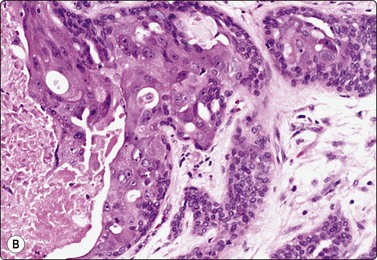

Fig. 4.7 Basaloid squamous cell carcinoma of head and neck

(A) Poorly differentiated cells with squamous features (MGG, HP; (B) Tissue section mimicking adenoid cystic carcinoma (H&E, IP).